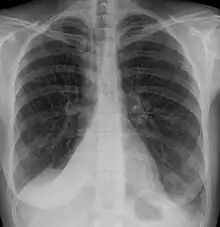

Atelectasis of a person's right lung

Atelectasis is the partial collapse or closure of a lung resulting in reduced or absent gas exchange. It is usually unilateral, affecting part or all of one lung.[2] It is a condition where the alveoli are deflated down to little or no volume, as distinct from pulmonary consolidation, in which they are filled with liquid. It is often referred to informally as a collapsed lung, although more accurately it usually involves only a partial collapse, and that ambiguous term is also informally used for a fully collapsed lung caused by a pneumothorax.[1]